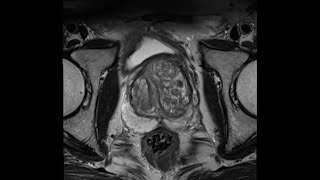

Introduction to Prostate MRI and PI-RADS: Approach and Principles

Introduction to PI-RADS Prostate MRI Introduction

Multi-parametric Prostate MRI using PI-RADS v 2.1: an Introduction Prostate MRI: Introduction PI-RADS v2.1 on MRI